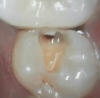

Figure 1 shows a pretreatment photograph of a tooth No. 20. In Figure 2, the circled area of the x-ray indicates the interproximal area where the clinician was uncertain if caries was present. Though x-rays are useful, transillumination is more sensitive and optimal for detecting caries in the early stages.12 With new devices, clinicians can acquire more information before working on the tooth. As shown in Figure 3, caries was confirmed using the transillumination system (CariVu), though it did not show up on an x-ray. The clinician was able to show the image to the patient. The open-tooth camera image then revealed the extent of the caries in the exact position that was displayed in the transillumination image (Figure 4). This is a significant advantage in minimizing preparations and saving valuable tooth structure.

Fig 4. Open-tooth camera photograph confirmed caries exactly where it was displayed on transillumination image.

Figure 4